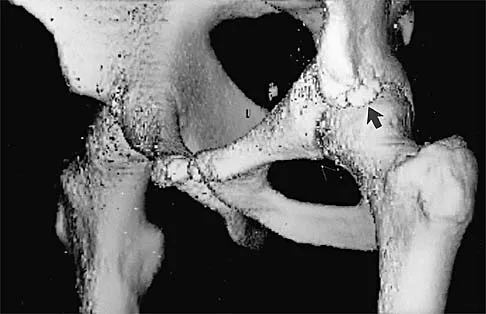

Question 35

A 42-year-old man reports the recent onset of right hip pain. A radiograph and MRI scan are shown in Figures 38a and 38b. A WBC count, erythrocyte sedimentation rate, and hip aspiration are within normal limits. Management should now consist of

Explanation